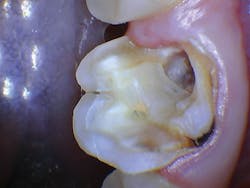

The patient was anesthetized with 1.7 ml of 4% articaine with epinephrine 1:100,000. The entire procedure was performed using the "Hard and Soft Tissue" setting. The gingiva was flapped to expose bone using the 0.25 mm spot size with 1% mist and cutting speed between 20% and 50% (figures 9-10). Only 0.5 mm of tooth structure was coronal to the alveolar bone. The osseous tissue was removed to establish biologic width and expose tooth structure coronal to bone for a proper restoration (figure 11). Proper positive bony architecture was maintained. The 0.75 mm spot size was used with 100% mist and cutting speed between 30% and 60%. A temporary restoration was placed, followed by one suture (figure 12). The total procedure time was 50 minutes. The patient was reevaluated after seven days (figure 13), and the final crown was placed (figure 14).

Figure 11: Flapped, postosseous reduction